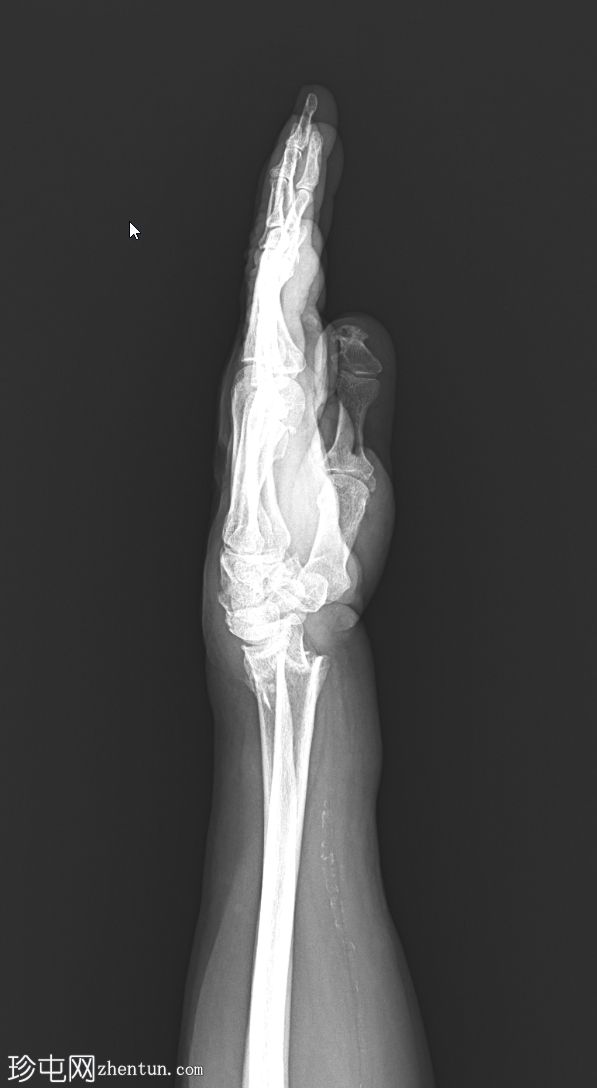

正位片

正位片:桡骨远端横行骨折,伴背侧移位和桡骨缩短。尺骨茎突处有轻微撕脱性骨折。腕骨对位良好。